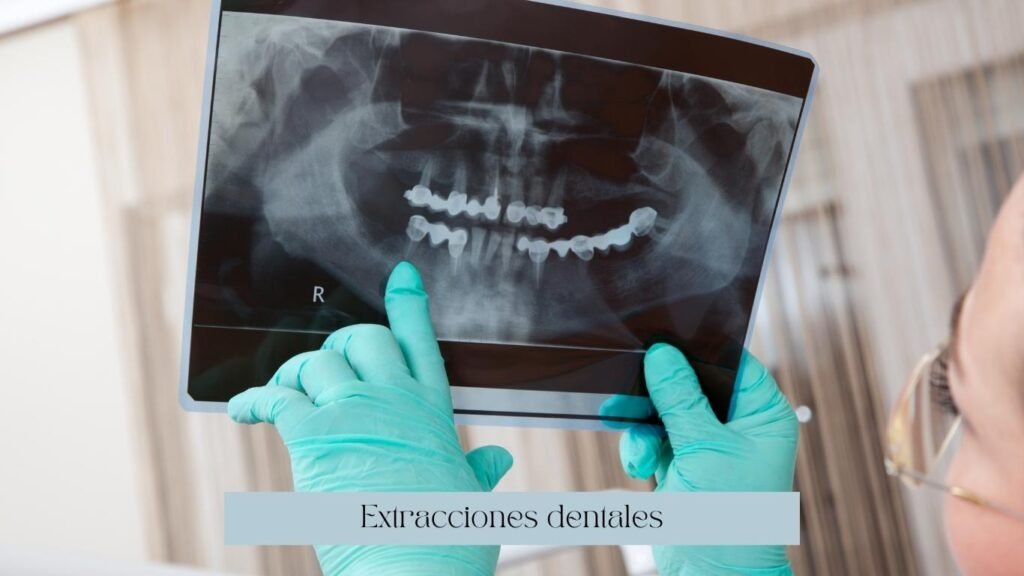

Extracciones dentales

Si tienes un diente con una infección que reincide frecuentemente, o con mucha movilidad o con alguna fractura significativa, probablemente no se pueda salvar tu diente. Nosotros podemos realizar en diagnóstico preciso y determinar si podemos preservar tu diente o si el único tratamiento que se puede realizar es la extracción dental.